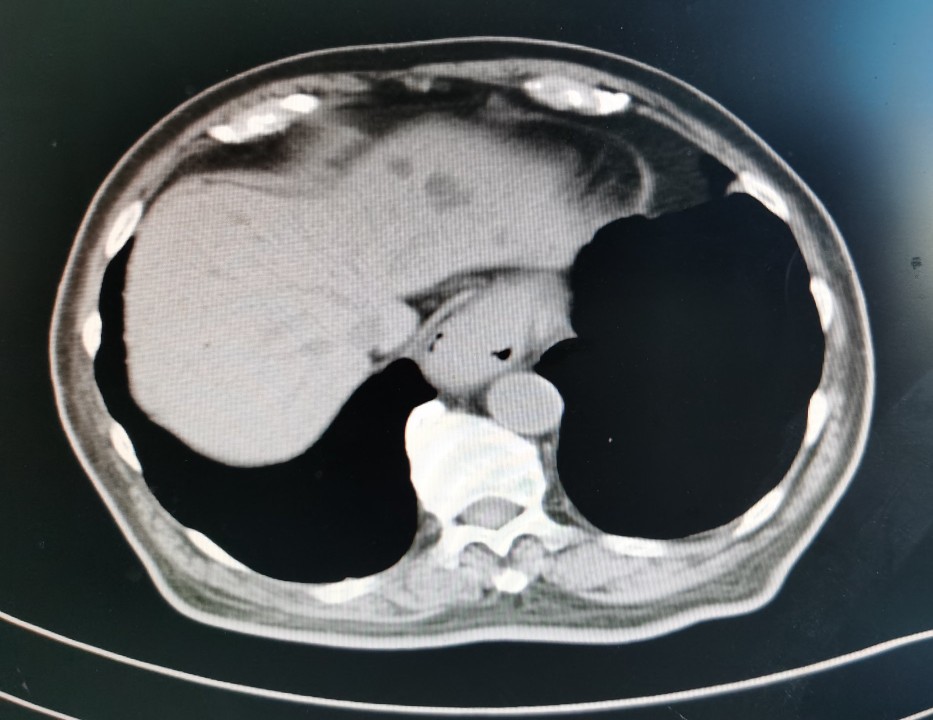

贲门部肿瘤CT表现

尽管病情危重,但王老非常坦然,好像把生死看的很淡,笑看人生总是尽力积极配合治疗。王老尽管年龄很大并且做过好几次手术,但是由于平时保养的不错,看上去偏年轻,并且住院后各种检查发现除心脏功能差一点,其它器官功能还可以。化验检查肿瘤标记物甲胎蛋白(AFP)特别高,超过9000ng/ml,考虑是种特殊类型的贲门癌,血色素63g/l,并且胃管里仍时有鲜血引出,腹部CT检查食管下段及贲门区占位,邻近淋巴结肿大,较上次检查明显增大,考虑为转移。因为病情重,连个增强CT都没敢做。